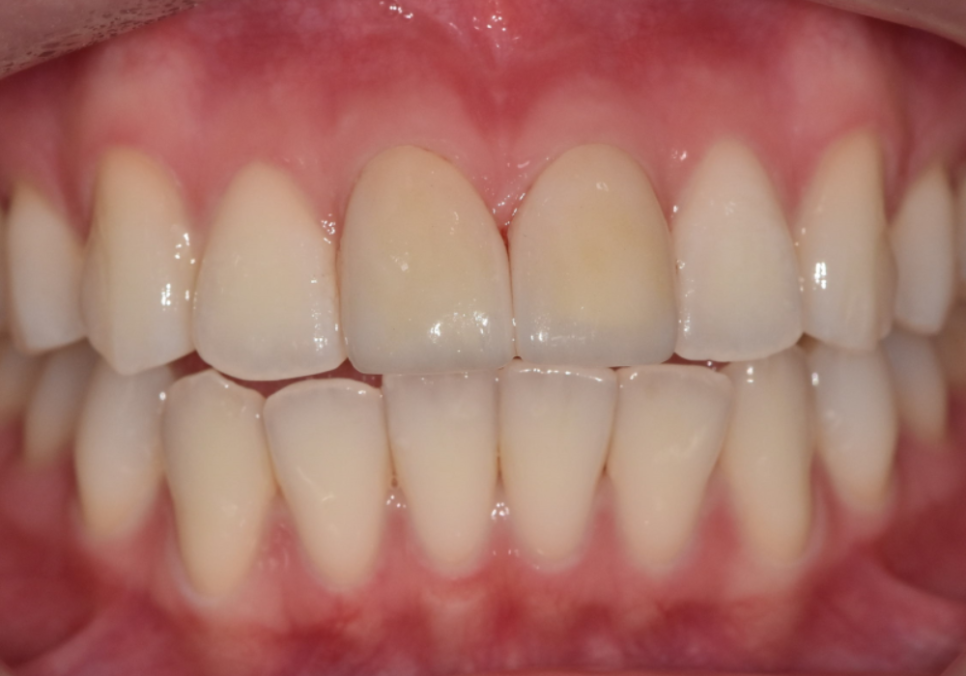

250410 절단교합으로 인한 앞니 레진 깨짐, 교정 없이 해결한 사례

250203(전) 250410(후)

최종 라미네이트를 부착한 모습입니다.

· 양쪽 앞니 길이가 가지런해지고

· 앞으로 뻗어 보이던 느낌도 자연스럽게 완화되고

· 절단교합에서도 힘을 덜 받도록 안정적인 공간이 확보되었습니다.

제가 계획했던 대로 라미네이트가 제작되어

저 또한 뿌듯했던 것 같습니다.